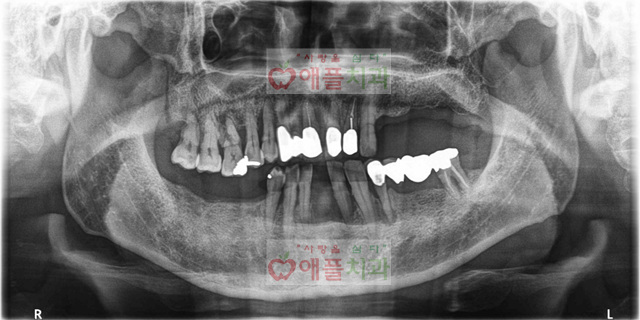

<임플란트 수술후>

5829274f62d7c.jpg

컴퓨터분석으로 하루만에 9개의 임플란트 시술을 받으셨습니다. 특히 아랫니 앞은 발치하면서 즉시 임플란트 시술하면서 당일 보철도 제작해드렸습니다.

직업때문에 치과 내원을 자주 못하신 분이셨는데, 당일 컴퓨터분석을 통해서 시술 받으시면서 심미적 만족을 드리면서 내원 횟수를 확~줄였습니다.